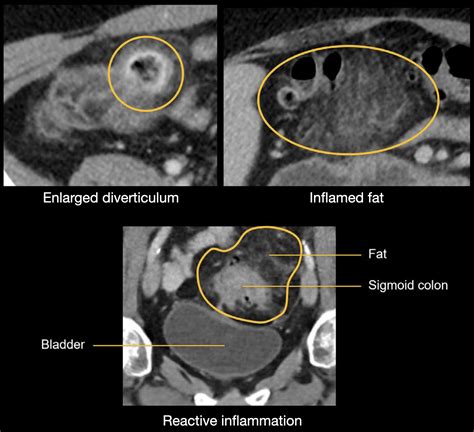

CT Urography Provides detailed 3D images to assess the surrounding structures and confirm diagnosis.